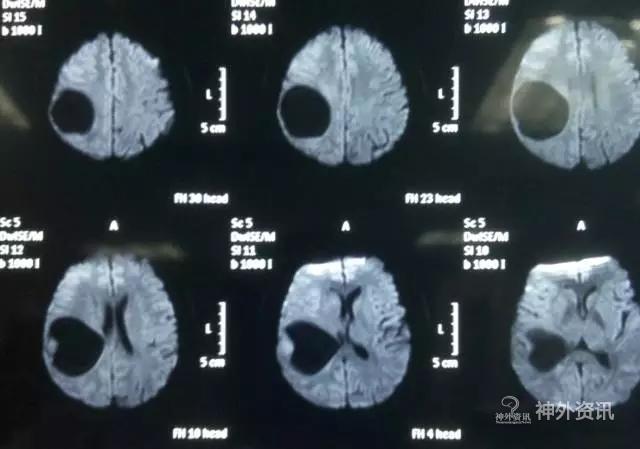

头颅MR示:右颞顶囊性占位伴结节,考虑胶质瘤可能。MRI T1为等信号(图1);T2囊液为高信号(图2);结节为均匀增强(图3);弥散相显示弥散受限(图4)。

图1. MRI T1为等信号。

图2. T2囊液为高信号。